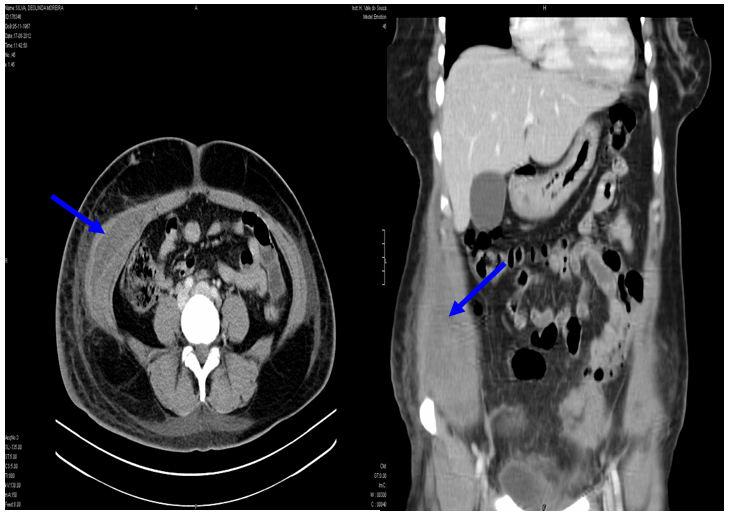

The patient was admitted to our department for expectant management, with recommendation to rest, and an application of ice packs on the hematoma site. She did oral analgesic, and antibiotic therapy was changed to piperacillin+tazobactam and clotrimazole. During the next 48 hours, the patient did not present fever, remained hemodynamically stable and the hematoma maintained the same dimensions. Further lab tests revealed hemoglobin 10g/dl, with stabilization of the inflammatory parameters. Control CT scan of the abdomen and pelvis on the 12th day after surgery showed an oblique hematoma with 55x45mm (Figure 2). The patient discharged the hospital on 20th. At follow-up appointment (3rd and 6th months after surgery), the patient was clinically well. Hemorrhagic dyscrasias were excluded, and the abdominal and soft tissues ultrasound didn´t reveal any anomalies.

Figure 2 Computerized tomography shows a slight asymmetry between the right and left oblique muscle (blues arrows).